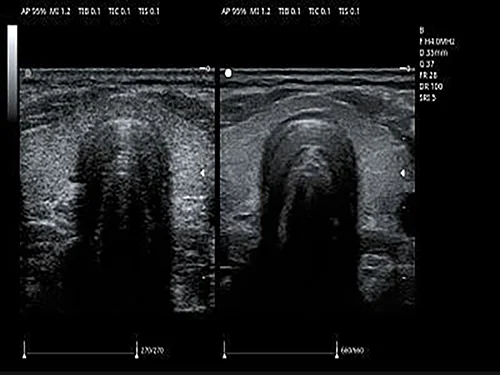

Линейный датчик 7L4PD

• Рабочая полоса частот: 4,2–15,0 МГц

• Количество элементов: 128

• Апертура: 38 мм

• Применение: сосуды (в т.ч. сонные артерии), поверхностные органы (ЩЖ, молочные железы), периферические нервы, MSK, ортопедия, яички, лёгочная диагностика, педиатрическая абдоминальная диагностика.

Spatial Compound Imaging

SCI - пространственный компаундинг обеспечивает подавление артефактов при исследовании.

Speckle Reduction Imaging

SRI - режим подавления зернистости в В-изображении